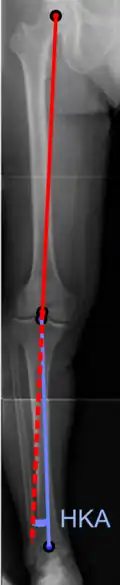

Hip-knee-ankle angle.

On projectional radiography, the degree of varus or valgus deformity can be quantified by the hip-knee-ankle angle,[9] which is an angle between the femoral mechanical axis and the center of the ankle joint.[10] It is normally between 1.0° and 1.5° of varus in adults.[11] Normal ranges are different in children.[12]